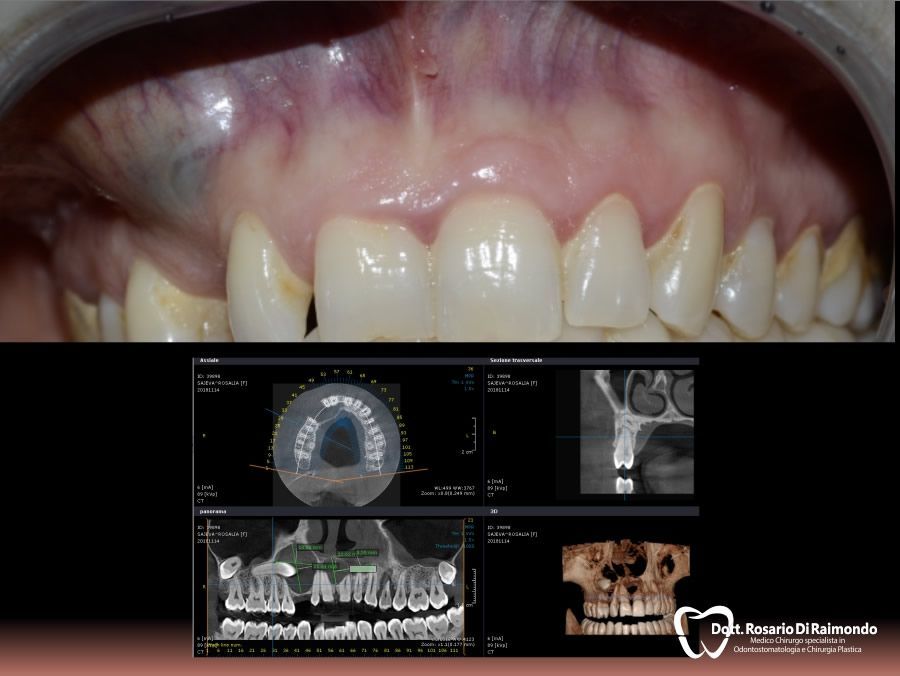

Casi Trattati

Di seguito riportiamo alcune fotografie di casi esplicativi di Chirurgia Orale.